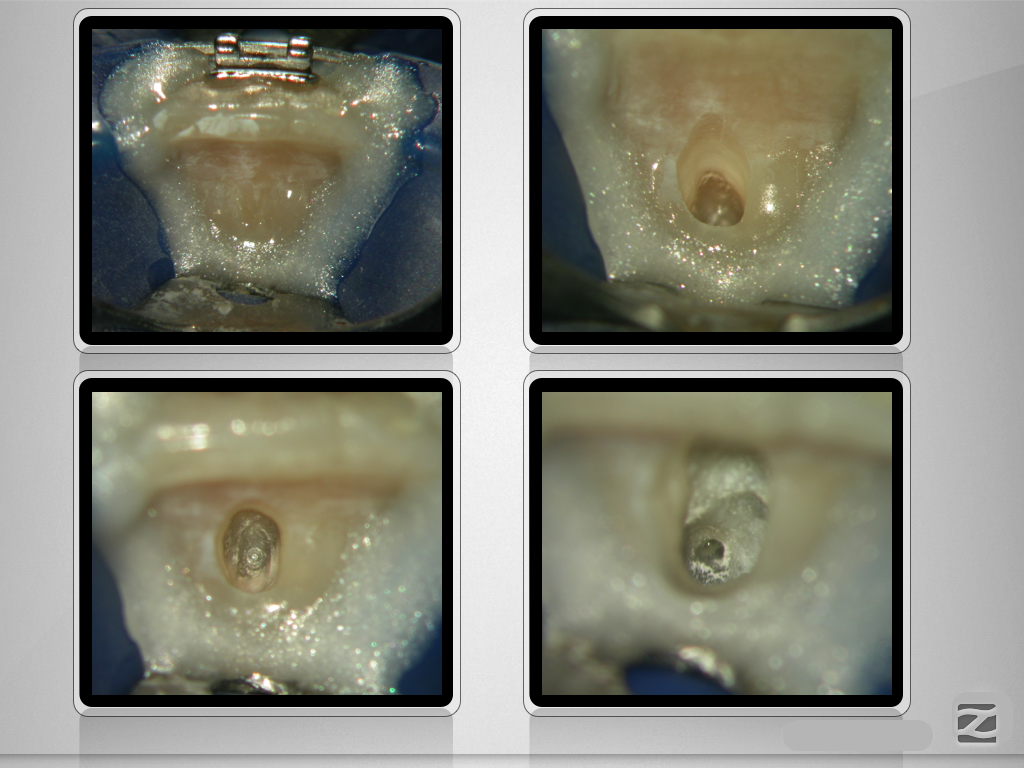

Folgen eines Milchzahntraumas (2)